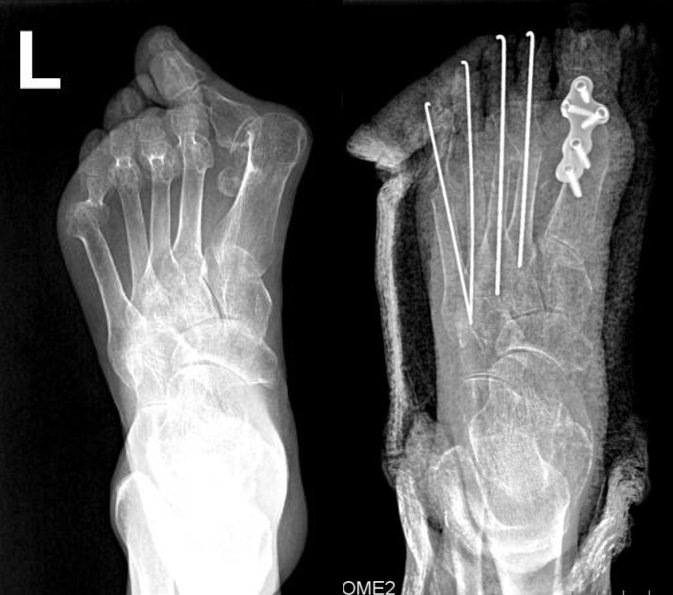

例4:罗XX,女,60Y。

左足:第1-5跖趾关节脱位,足拇外翻。

术式:左足:第1跖趾关节融合+第2-5跖趾关节成形术;右足:第4趾间关节融合+第5跖趾关节成形术